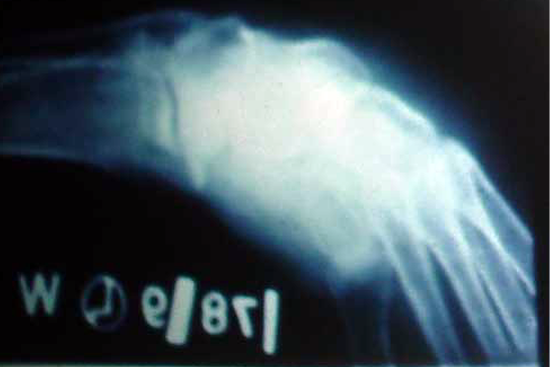

TEV

Gulam Rasul